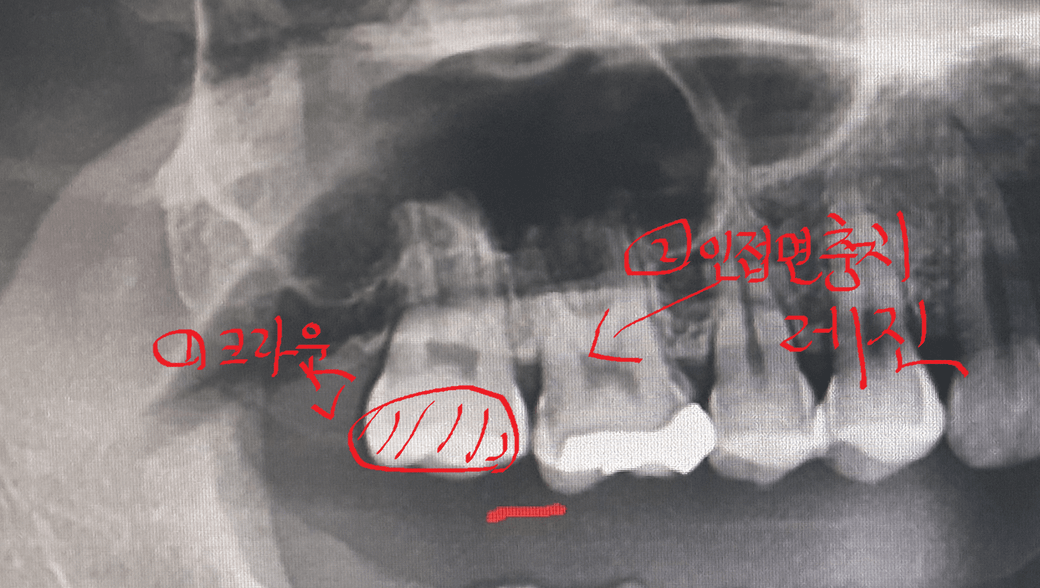

2021년 10월 중순 17번 치아 크랙증상 발생으로 치과 방문 했는데

17번 치아 크라운 치료 진행 하려고 치아 많이 깎는 도중에

16번 치아 인접면 충치가 발견되서 인접면 레진 치료를 받았습니다.

그리고 나서 17번 치아 신경치료 없이 골드크라운 씌우고

사진상으로 보면 16번 치아의 원심면 부위에 충치가 깊어 보입니다. 기존에 인레이치료를 한상태이고, 17번과 붙어 있는 상태이기 때문에 17번 치아를 삭제하는과정중에 16번 우식이 보여서 치료를 권장한거 같습니다. 충치가 깊어서 신경에 자극이 가서 치아가 시릴수도 있습니다. 일시적인거일수도 있고, 신경에 자극이 가서 시릴수도 있으니 당분간은 지켜보시는게 어떠신지요.

1. 원래 16번 원심면 충치가 깊어보인다.

2. 17번 치아 삭제시 충치가 보여 충치치료를 권장

3. 충치가 깊어서 치료후 시린증상 나타남으로 정리해볼수 있겟네요.